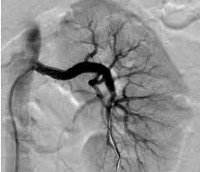

Контрастно-индуцированный вариант нефропатии у пациентов с нормальной функцией почек встречается не более чем в 0,5-5% исследований с использованием непроницаемых для йода рентгеноконтрастных препаратов. Вероятность развития расстройства значительно возрастает при наличии факторов риска. Таким образом, по результатам клинических наблюдений в области современной урологии, после компьютерной томографии различных органов, периферической и сердечной ангиографии, почечная дисфункция той или иной степени проявляется у 50-90% пациентов с диабетической почечной паренхимой.